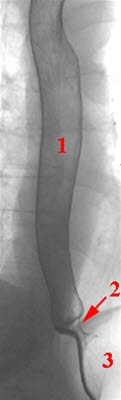

Øsofagus og nedre sphinkter framstilt med dobbelkontrast-teknikk

- Øsofagus (spiserør)

- Nedre sphinkter

- Magesekk